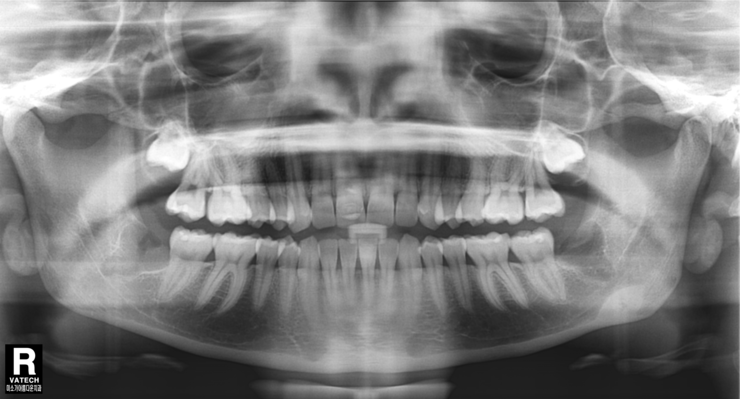

오른쪽은 왼쪽에 비해서 비교적 쉬운 경우이지만

그렇도 이런 사랑니 발치는 상당히 어려운 난이도입니다.

사랑니를 뽑고 난 뒤 엑스레이 사진입니다.

주변의 잇몸뼈를 전혀 건드리지 않고 깔끔하게 발치가 되었습니다.

사랑니를 뽑은 후 엑스레이 사진입니다.